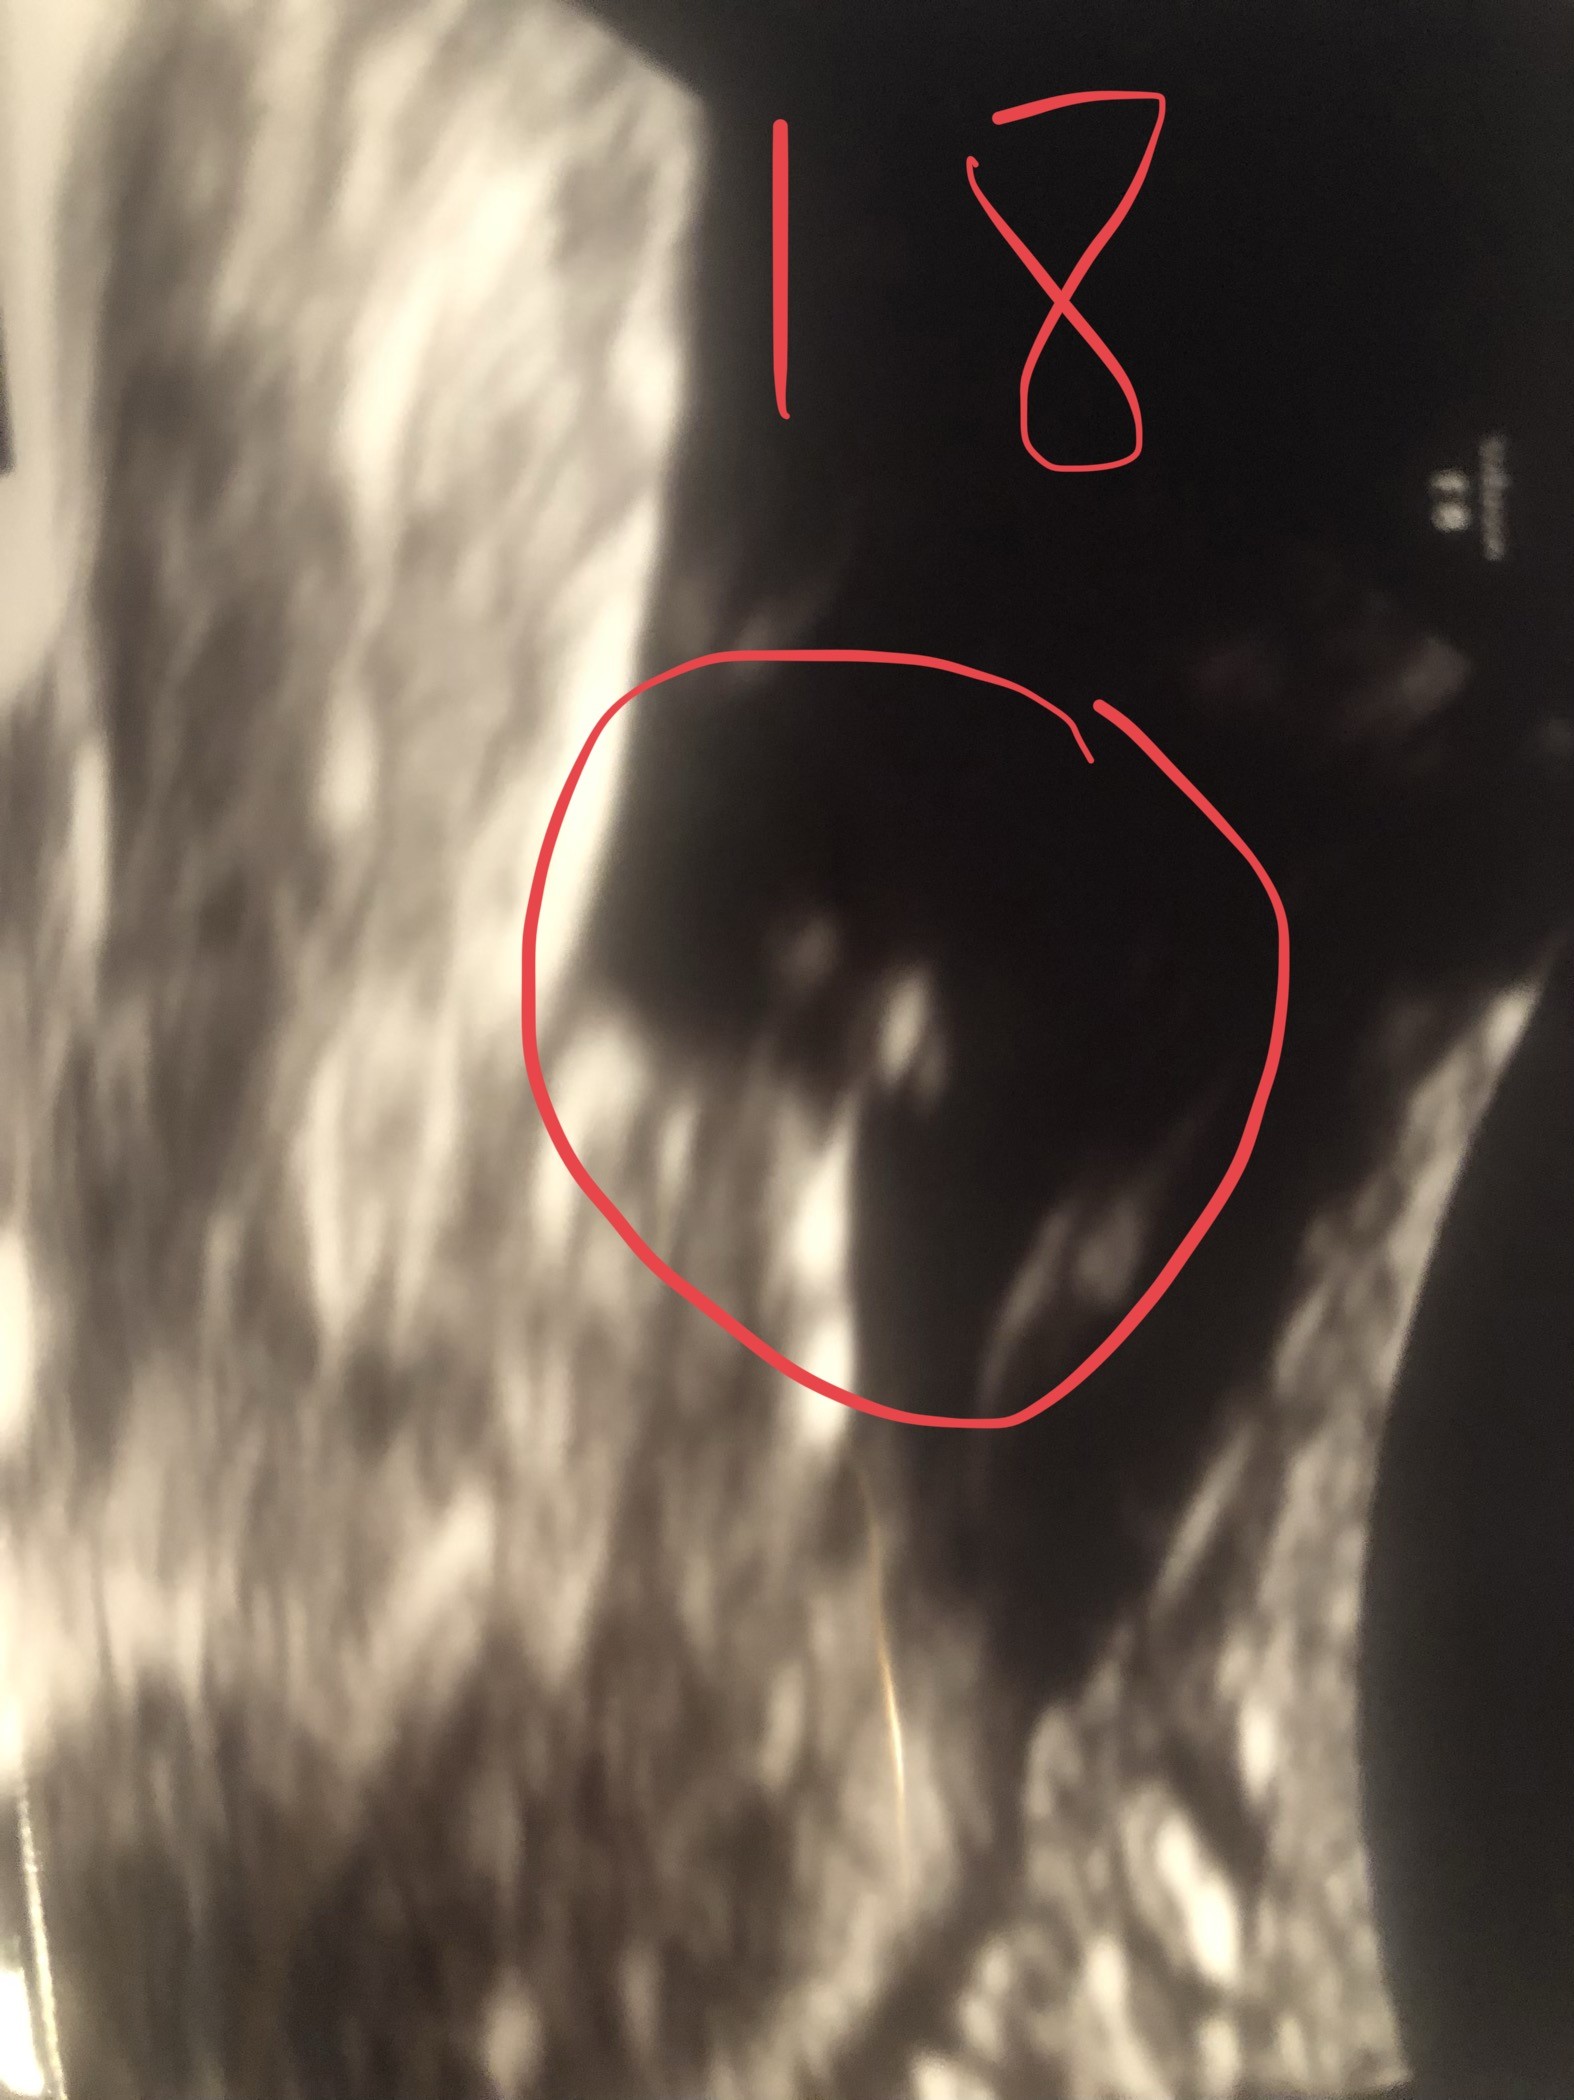

Witam w 19 tygodniu ciąży dowiedziałam się ze będę miała dziewczynkę w 20 tyg okazało się jednak , że to chłopak. Sama już nie wiem bo na jednym usg widać na pewno dziewuche a na drugim chłopca. Może to pempowina ?? Może ktoś mi pomoże rozwiązać ta zagadkę